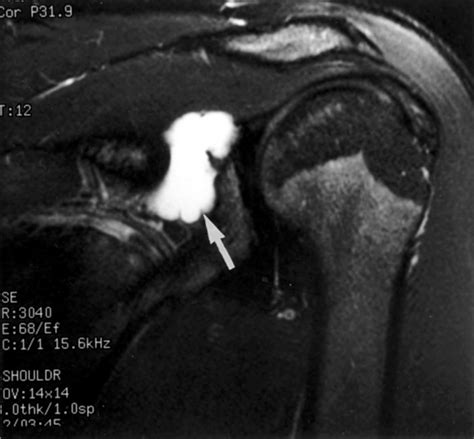

• slap tear with paralabral cyst

• paralabral cyst

• cyst in shoulder rotator cuff